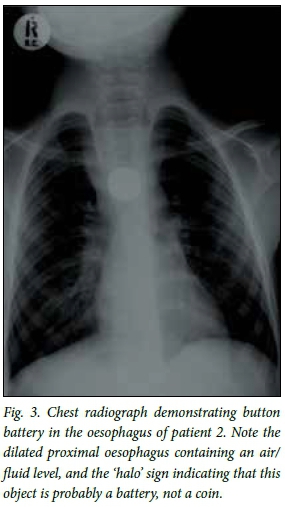

A 6-year-old girl was taken to a general practitioner after swallowing a watch battery. The family was told that as long as she was passing stool normally, the battery would pass and that they need not worry about it. A year later she presented again with dysphagia and symptoms of aspiration (coughing after feeds and recurrent respiratory tract infections). A chest radiograph revealed a foreign body in the oesophagus (Fig. 3). The oesophagus proximal to this was dilated and had an air/ fluid level, and the lung fields showed features suggestive of aspiration pneumonia. A CT scan revealed a foreign body lodged posterior to the oesophagus and medial to the arch of the aorta (Figs 4 and 5).

In the case of oesophageal impaction, a chest radiograph will reveal a smooth, round object, most commonly lodged in the cricopharyngeal area, in the middle third of the oesophagus where the left main bronchus crosses the oesophagus (as this is anatomically the most narrow part of the oesophagus) or at the lower oesophageal sphincter.[2] The most commonly ingested foreign body is a coin,[1,2,13,14] and if the ingestion went unwitnessed the battery may be mistaken for a coin on a plain radio-graph.[12,13] Clues that one may be dealing with a button battery rather than a coin may be found on the lateral film, where one side of the battery is perfectly flat while the other is convex,[13] and one may see the 'step-off' sign, which refers to the 'step' between the battery and its casing.[11] In addition, on a well-exposed film there is a rim of lucency on the inside edge of the battery,'131 also known as the 'halo' sign (Fig. 3).[11]